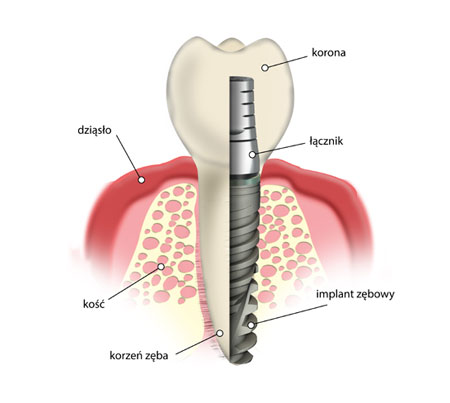

Implant w sposób sztuczny zastępuje korzeń zęba. Jest umieszczany w kości szczęki lub żuchwy i tworzy podstawę do zamocowania korony.

Ma postać małej śrubki, najczęściej wykonanej z tytanu. Ząb sztuczny oparty na implancie poprzez analogię zamocowania do zęba naturalnego pozwala zapewnić stabilność oraz pełną funkcjonalność implantu, porównywalną z zębami własnymi.

Wszczepiony implant wraz z osadzoną na nim koroną zastępuje brakujący ząb pod względem funkcjonalnym, jak i estetycznym. Jego istotną cechą jest długa żywotność, powinien utrzymywać się tak długo, jak długo istnieją otaczające go struktury tkanek. Obecnie stosowane implanty zapewniają biokompatybilność, czyli struktury tkanek go otaczające nie ulegają uszkodzeniu, a wręcz przeciwnie, implant działa stymulująco i zapobiega procesom zanikowym kości, jej resorpcji.